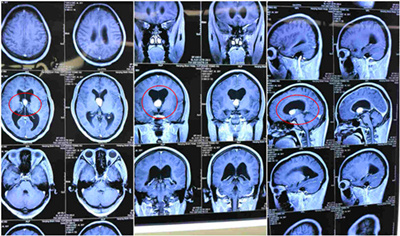

术前CT影像资料:不同截面,红圈内白色物体为肿瘤物